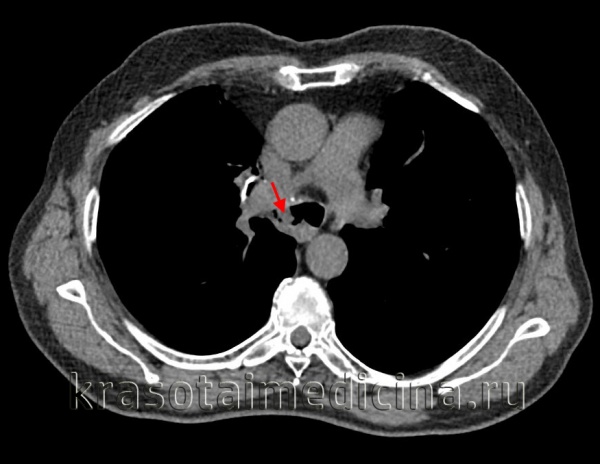

КТ органов грудной клетки. Стеноз правого главного бронха за счет мягкотканного образования в его просвете.